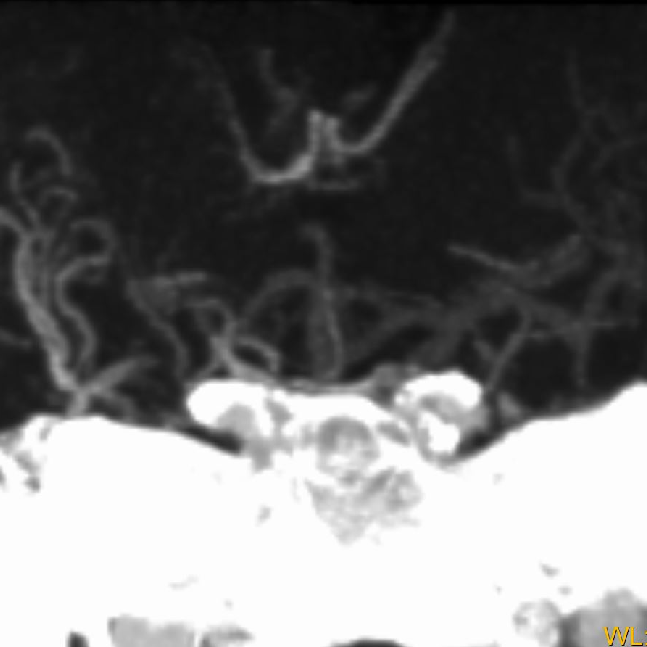

术前CTA:

CTA提示右侧大脑中动脉闭塞,左侧A1纤细。

延迟CTA扫描可见造影剂逆流至大脑中动脉主干。